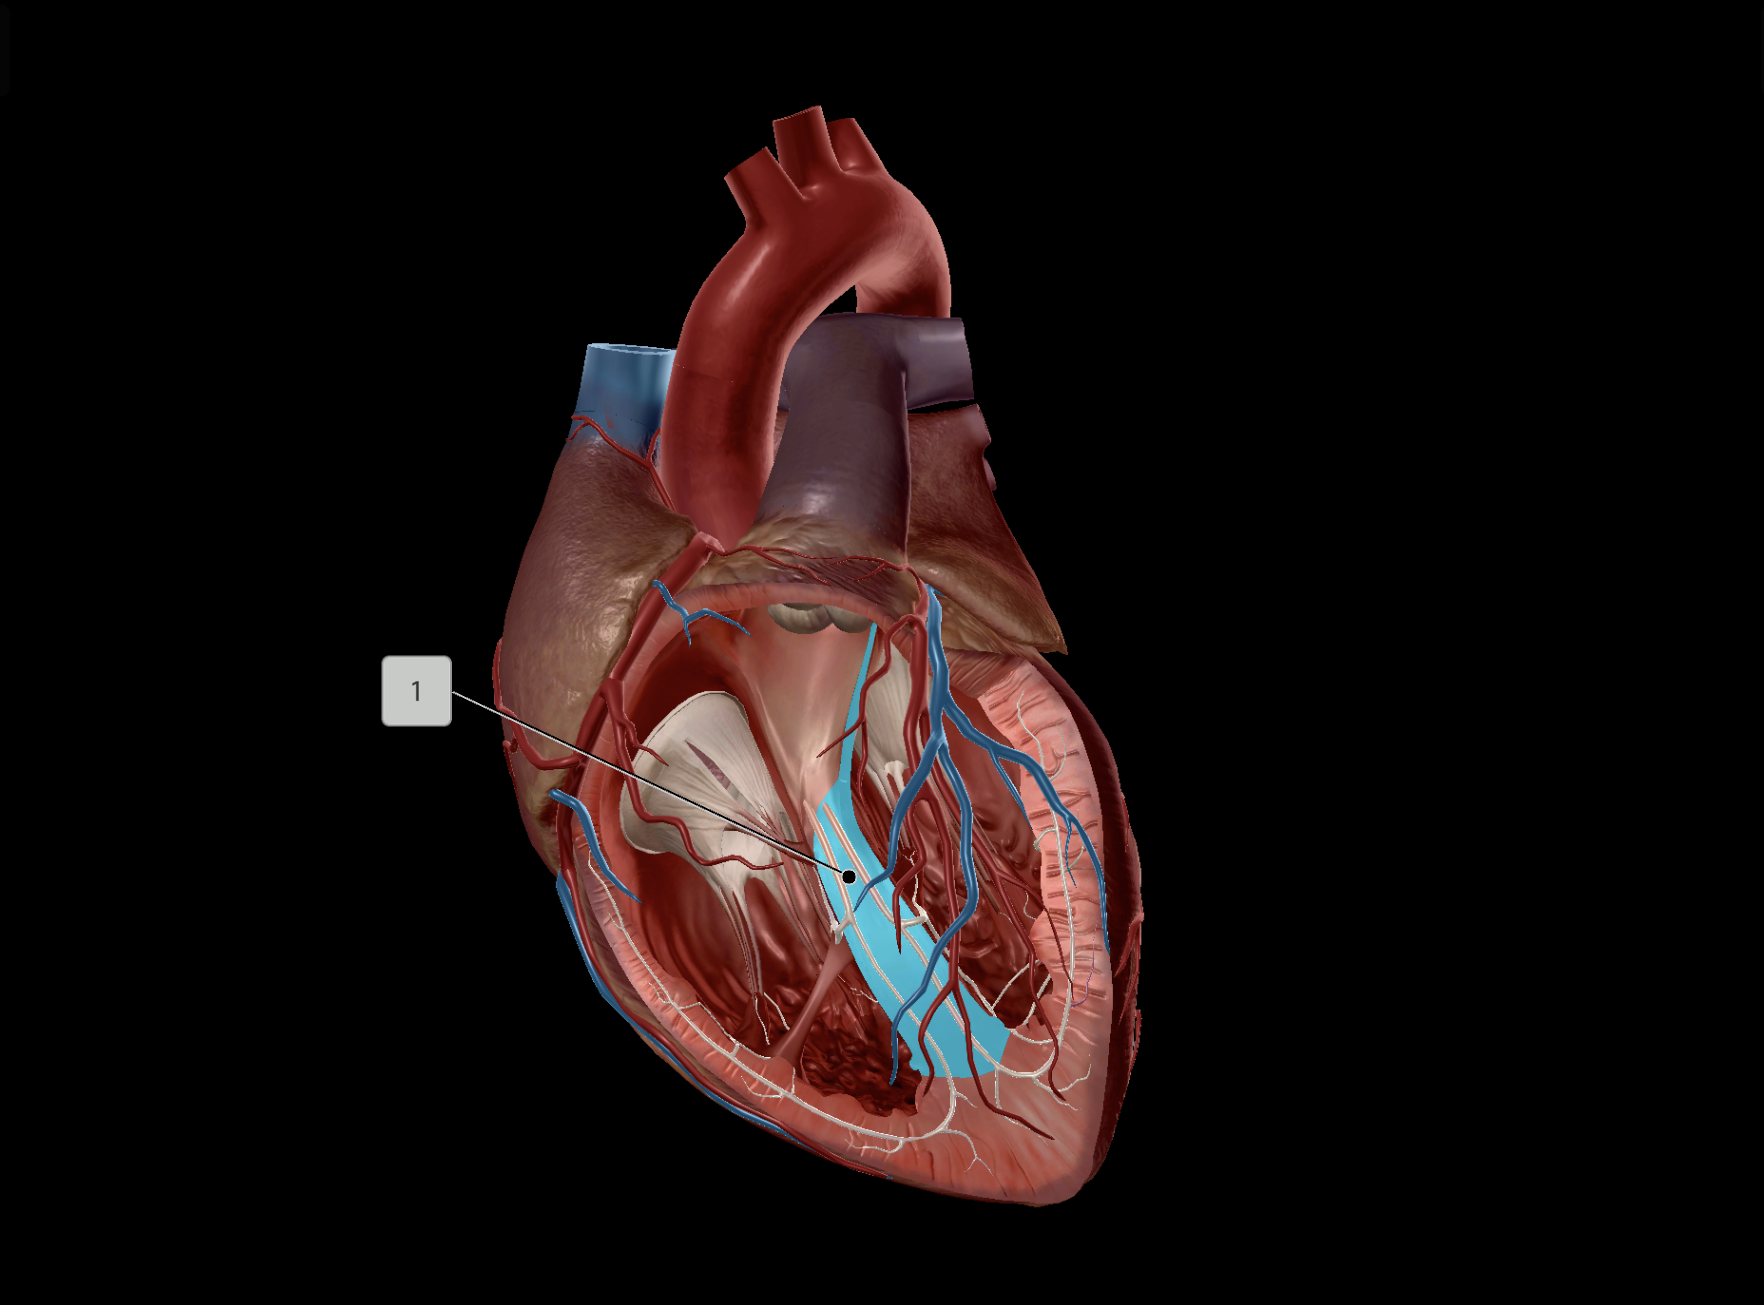

Papillary Muscle

Interventricular Septum

Chordae Tendineae

Anterior Interventricular Artery

Middle Cardiac Vein

Anterior Interventricular Sulcus

Coronary Sulcus

Posterior Interventricular Sulcus/Artery

Great Cardiac Vein